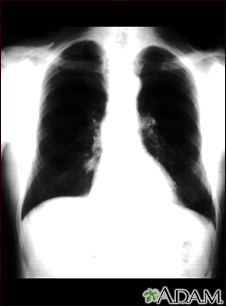

Nódulo pulmonar: vista frontal en la radiografía de tórax

Nódulo pulmonar - Vista frontal de la radiografía de tórax

Ésta es una radiografía del tórax que muestra una masa en la parte inferior del pulmón derecho, cerca al corazón (se puede observar del lado izquierdo de la imagen).